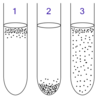

26-year-old woman returns from a safari vacation in Tanzania with fever and body aches. She received no vaccines prior to her trip and did not take malaria prophylaxis. Her blood smear is shown. What infection does she have?

A. Plasmodium falciparum

Infects many RBCs, causes clumping of RBCs

- P. vivax* does not cause clumping, infects <2% of RBCs (reticulocytes only)

- Trypanosoma* would be in its wiggly form (trypomastigote) in the blood

- Leishmania* don’t live in the blood